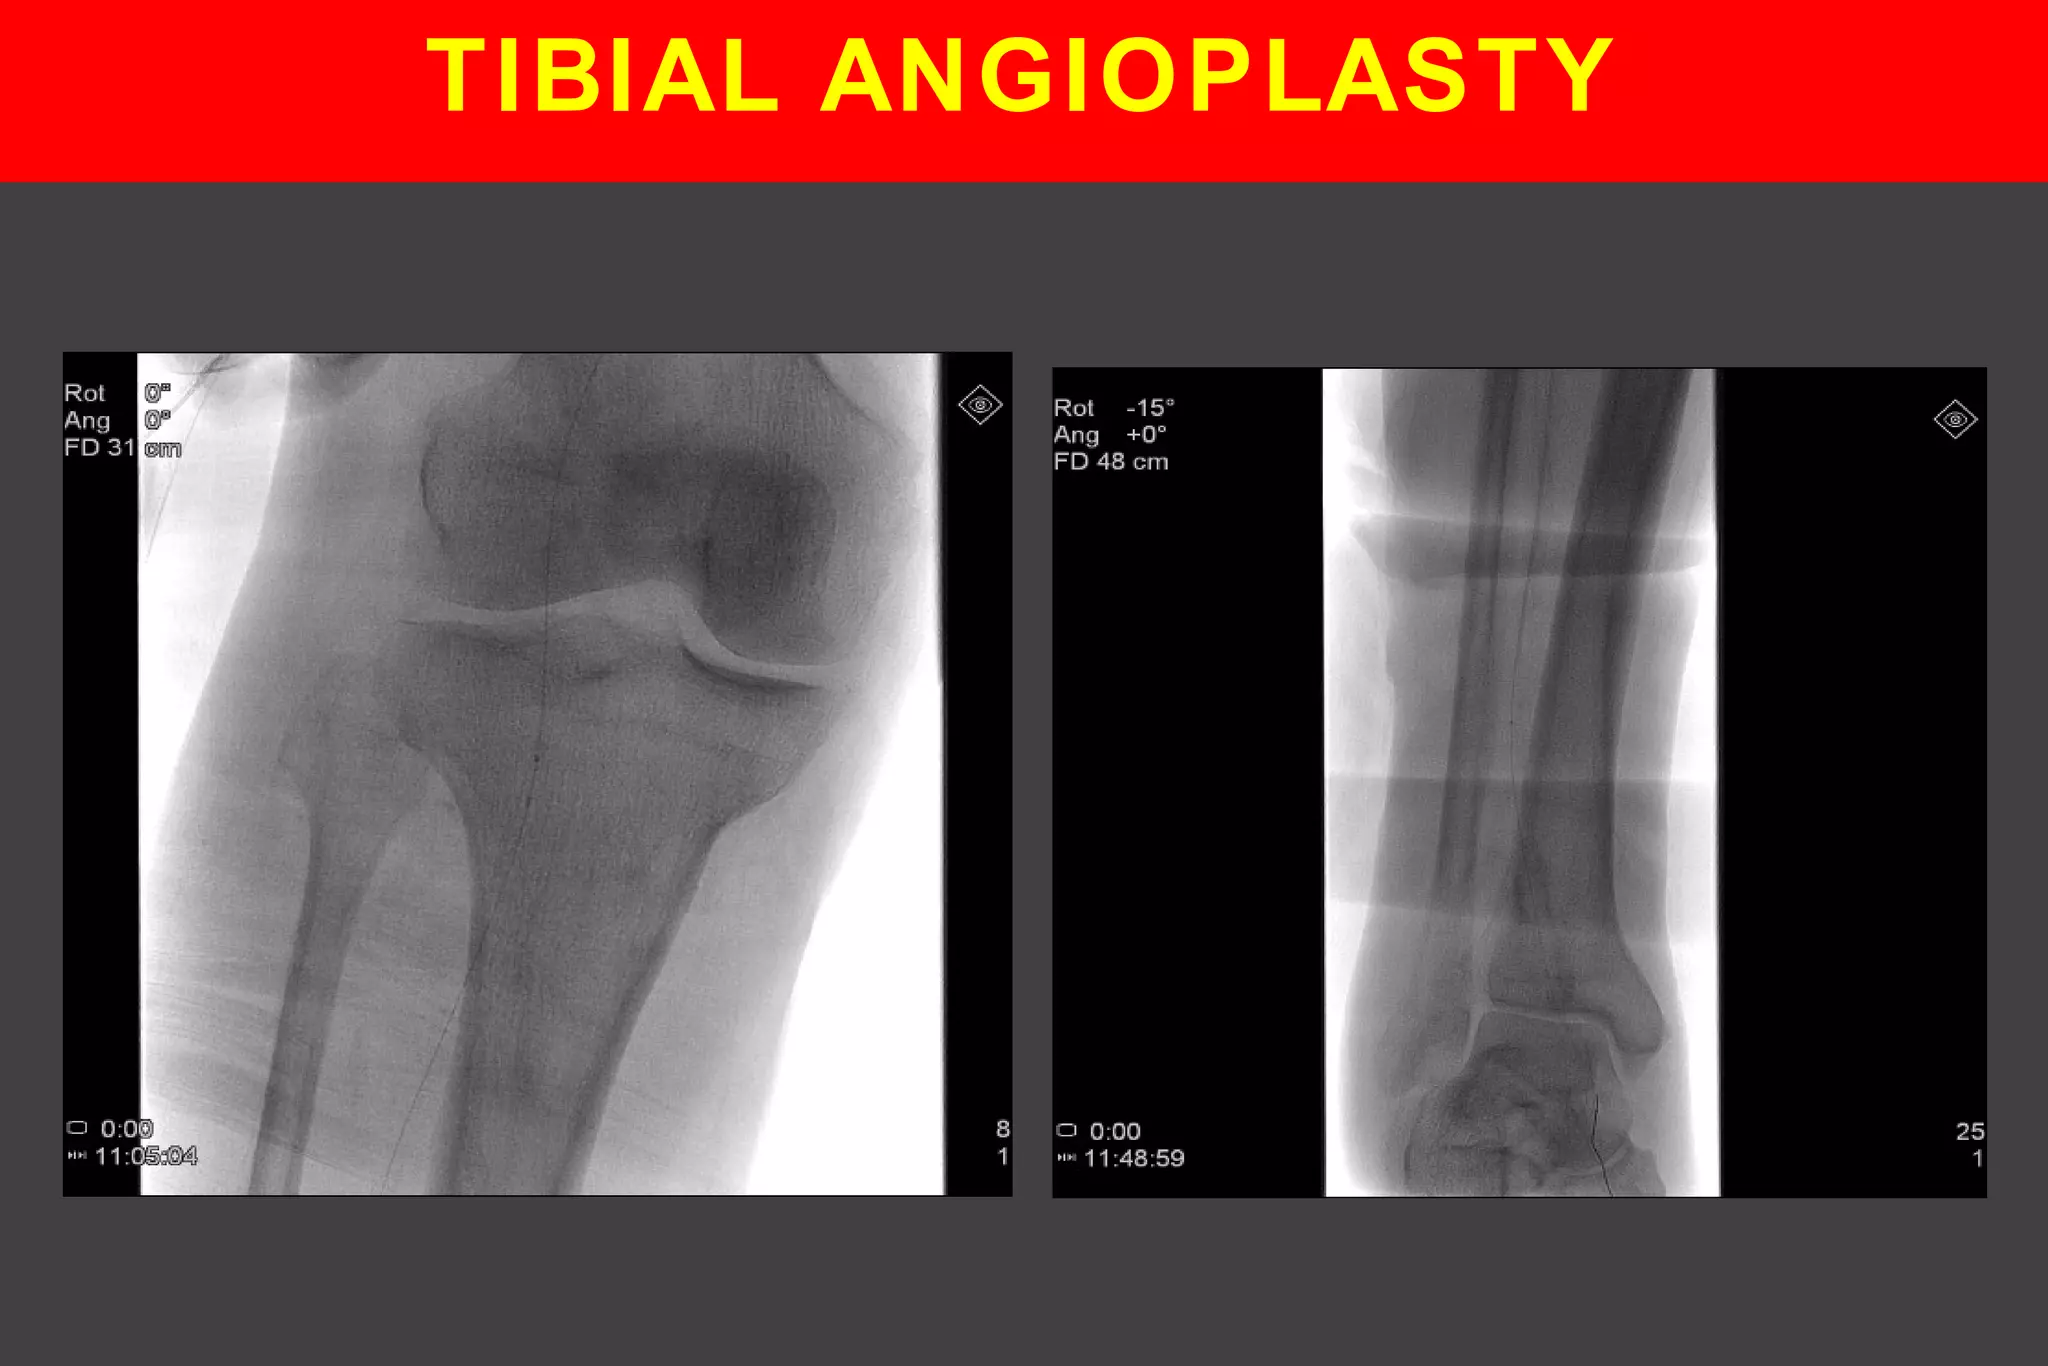

TIBIAL ANGIOPLASTY

TIBIAL ANGIOPLASTY - RESULT

PRE PER POST